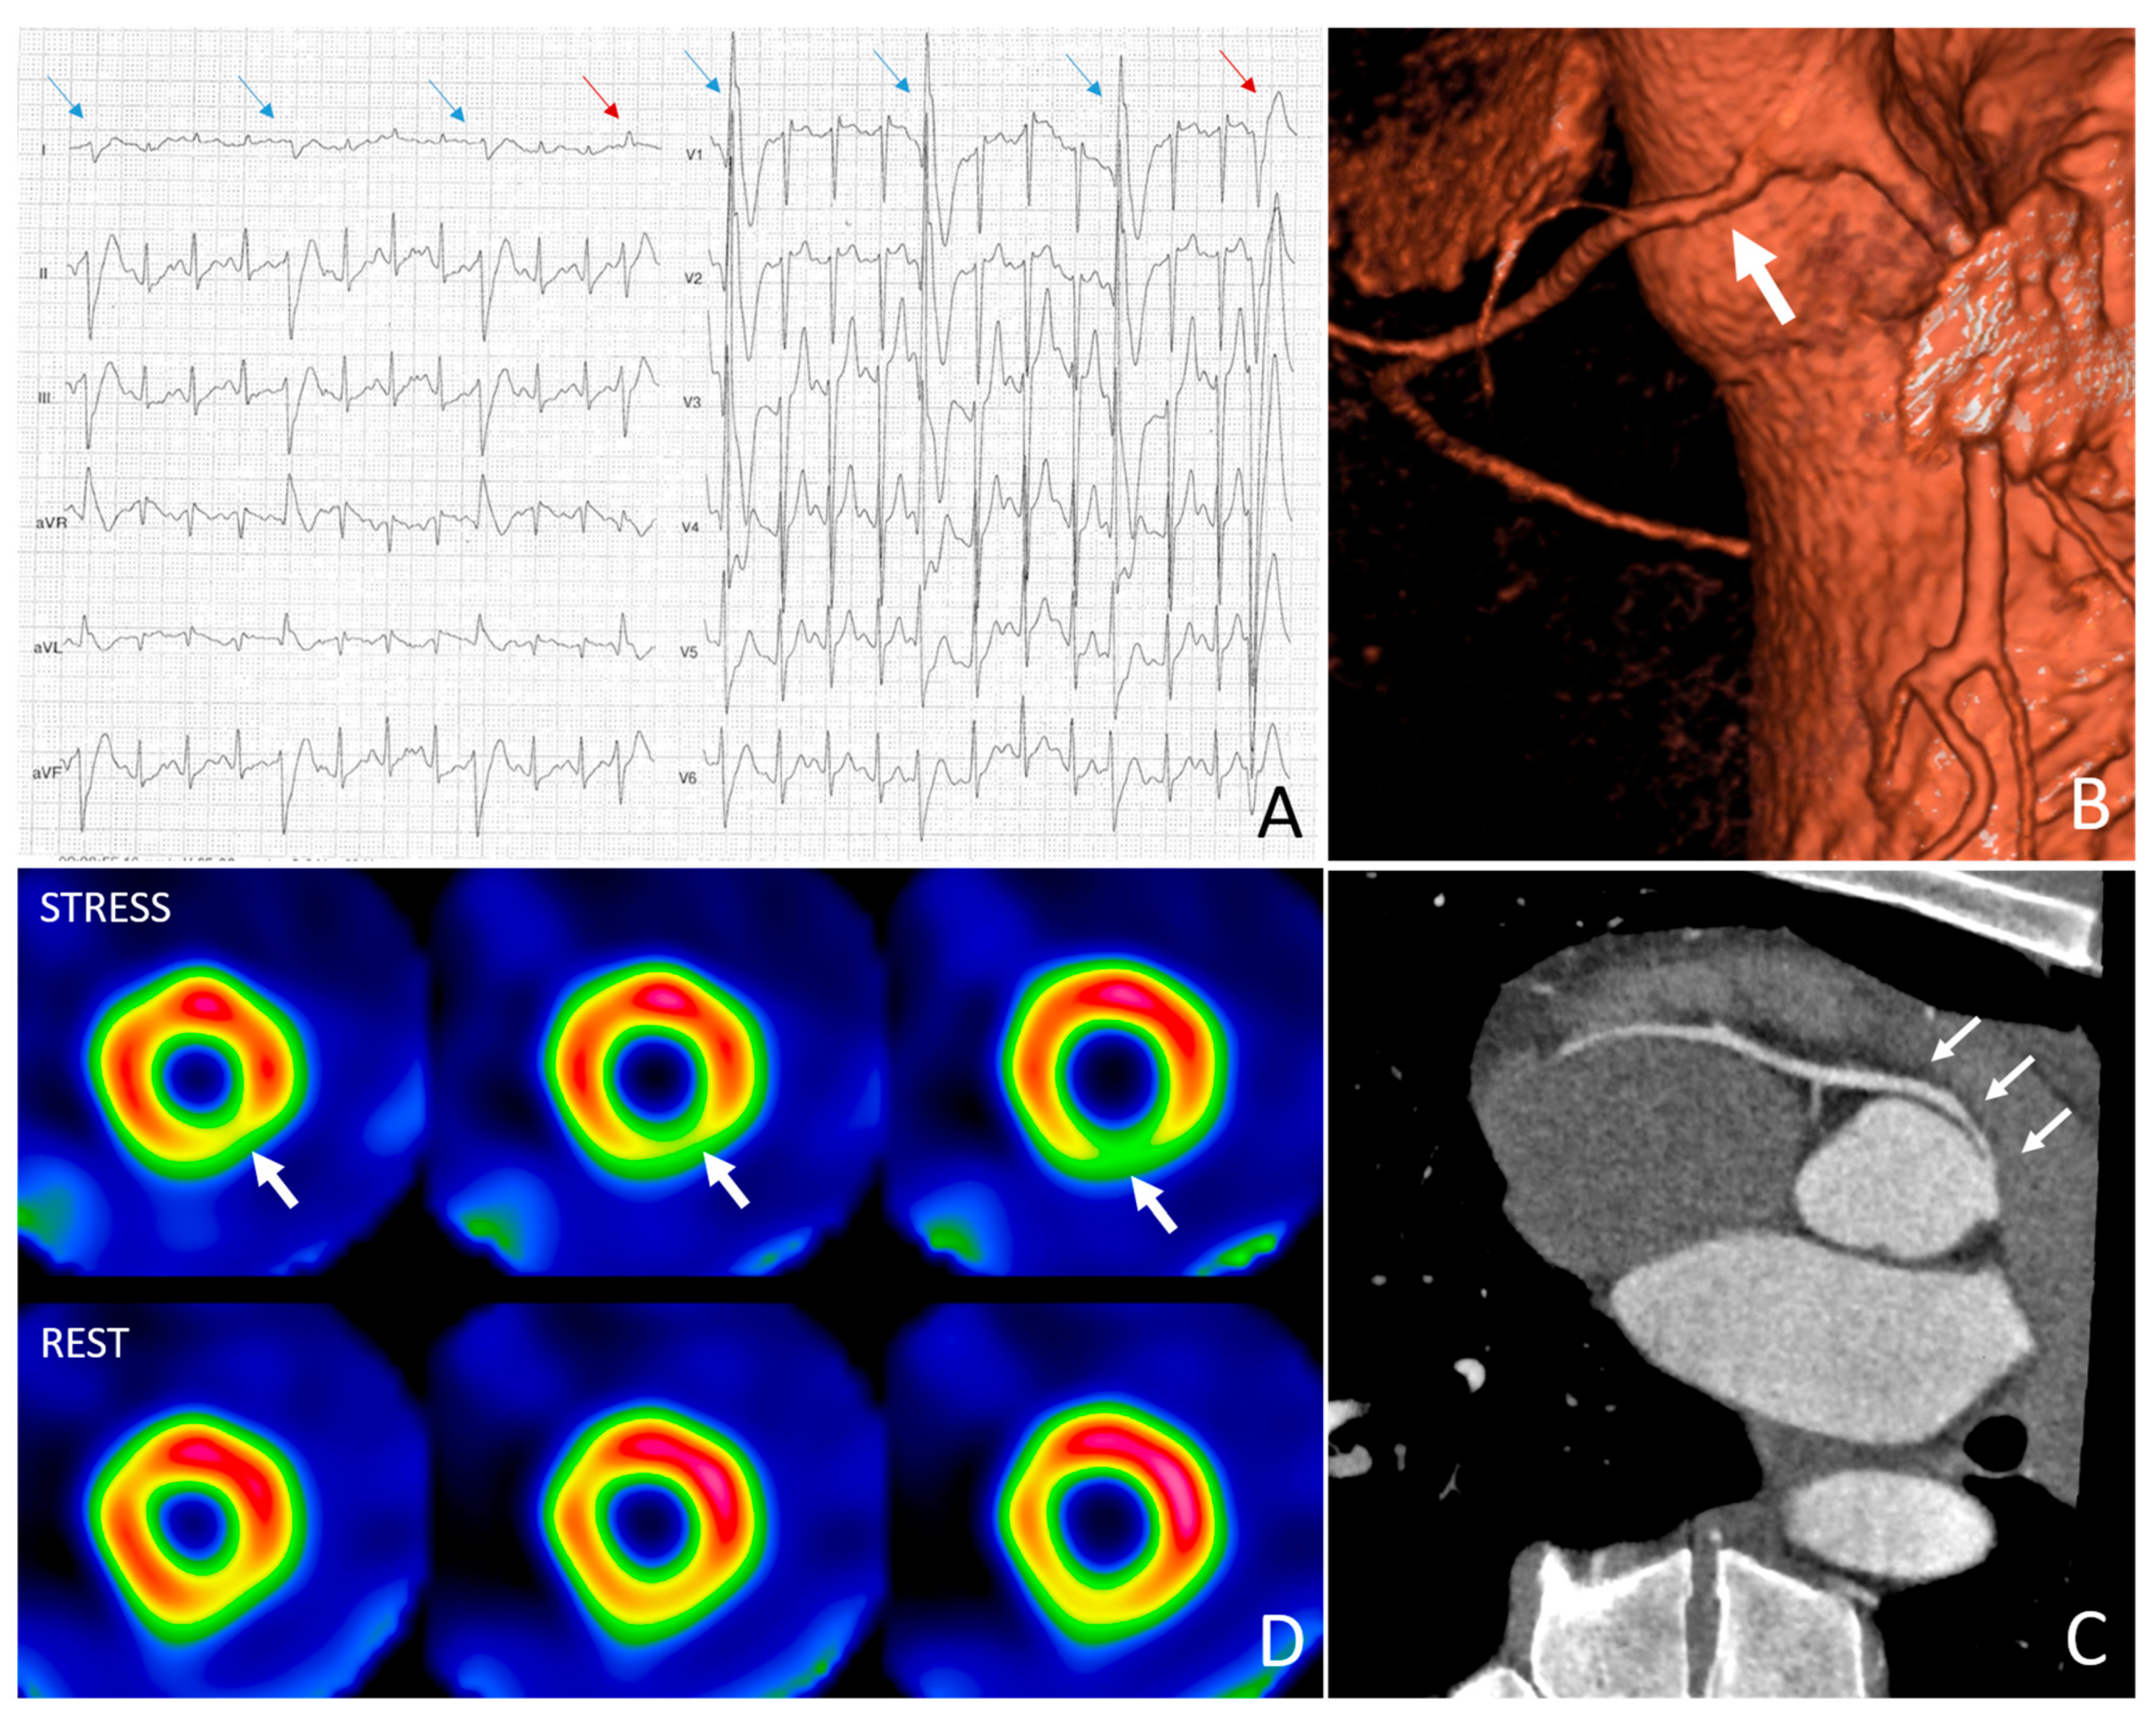

4.3. Athlete with Anomalous Origin of the Coronary Arteries with Interarterial Course

4.4. Athlete with Ventricular Arrhythmias and Late Enhancement on Cardiac MRI Suspected for Cardiac Sarcoidosis